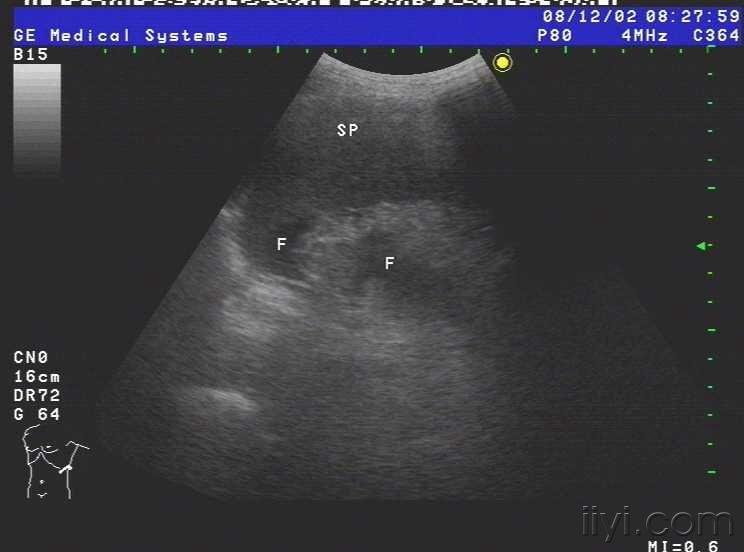

患者女,69岁,病毒性肝炎病史三年余,近半月自觉腹部胀满,来我院就诊,超声查示肝脏被膜不光滑,呈锯齿样,肝内回声不均匀,肝内多发小中等偏强回声团块,大小约1.5cm-3.0cm不等,无明显包膜,境界较清,另于肝右前叶近肝表面见一个大小约4.5cmx2.4cm的椭圆形实性低回声团块,至此处被膜略隆起,团块无明显包膜,伴侧方声影,后方回声增强,内部回声均匀,CDFI未见血流信号.右叶内另见两个类圆形囊性无回声区,肝内管道结构显示不清,肝门脉主干内径约1.1cm.胆囊壁厚1.0cm,囊内透声尚可,脾脏轻度增大,脾门脉无扩张;平卧位腹腔扫查于肝上前间隙肝肾隐窝脾肾隐窝双髂窝均见液性暗区.超声提示:1.肝硬化肝内多发实性团块合并胆囊炎脾轻大及大量腹水;考虑不除外肝癌?